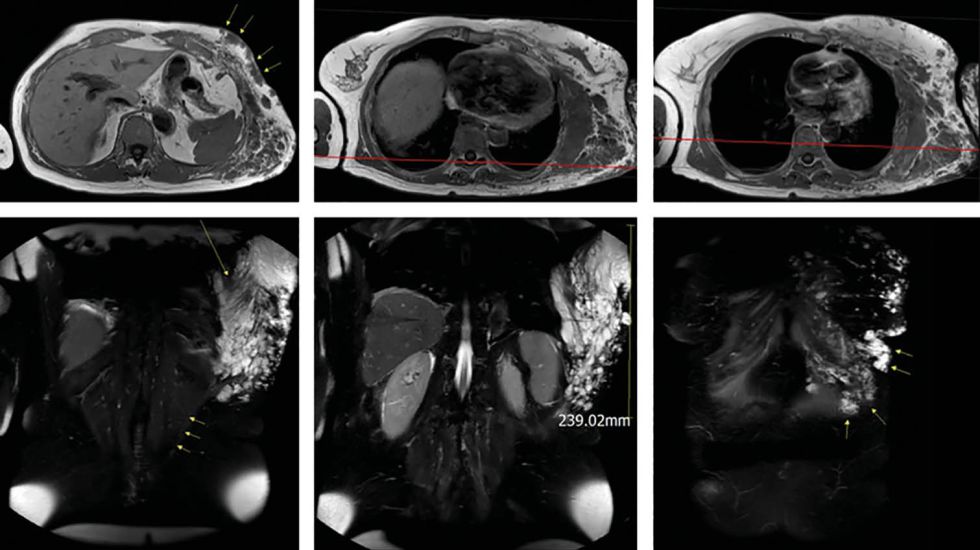

Laparoskopische Cholezystektomie für symptomatische Cholezystolithiasis (CCL) bei „Kasabach-Merritt-Syndrom“ (KMS)